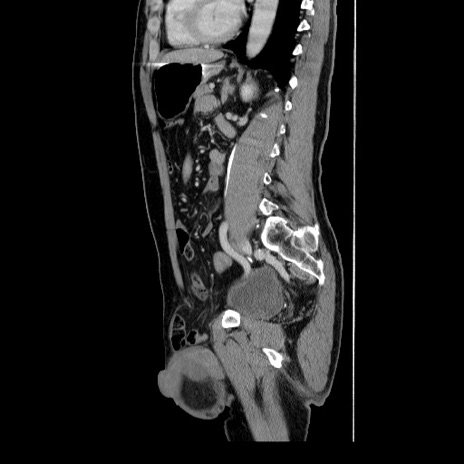

症例34(矢状断像)

【症例】60歳代 男性

【主訴】右鼠径部膨隆

【現病歴】1年程前より右鼠径部膨隆あり。自己にて還納可能だったため放置していた。3時間前より右鼠径部の脱出を認め、還納困難となり受診。

【既往歴】高血圧

【身体所見】右鼠径部に小児頭大の膨隆あり。弾性硬であり、用手還納は困難。左鼠径部にも膨隆を認める。脱出はなし。

【データ】WBC 15500、CRP 測定なし